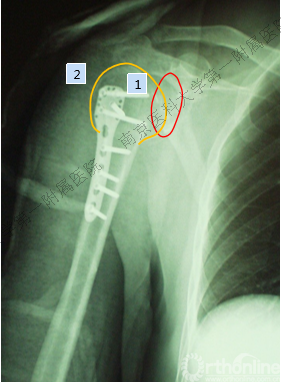

术后肩关节X线正位片

Ⅰ型: +肱骨颈骨折。

Ⅱ型: +肱骨颈骨折+小结节骨折(病例3)。

Ⅲ型: +肱骨颈骨折+小结节骨折+大结节骨折(病例2),以骨折线向肱骨近端外侧壁延伸为另一特征。